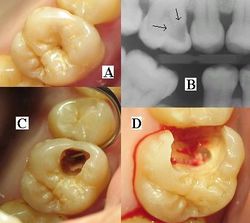

هو تخرب يصيب نسج السن الصلبة بدءاً من طبقة الميناء enamel ثم يصل إلى طبقة العاج محدثاً حفرة قد تزداد اتساعاً وعمقاً لتصل إلى اللب الذي يحتوي الأوعية الدموية والأعصاب.

حدوث التسوس وتطوره

تقوم الحموض الناتجة من عملية تخمر السكاكر بحل العناصر المعدنية والعضوية التي تدخل في تركيب ميناء السن فتبدو المنطقة بيضاء طبشورية وذات ملمس خشن. ولدى تزايد إنتاج الحموض وعدم تطبيق الفلوريد الموضعي على الأسنان الذي يقوم عادة بإيقاف تطور التسوس، يتهدم الميناء وتصل الإصابة إلى العاج مشكلة حفرة التسوس التي يمكن ملاحظتها سريرياً ويبدأ الإحساس بالألم لدى التعرض إلى مؤثرات خارجية من سخونة وبرودة أو الضغط أثناء المضغ. عند إهمال معالجة التسوس في هذه المرحلة يزداد التخرب وتصل الإصابة إلى لب السن الذي يصاب بالالتهاب وترافقه موجات حادة من الألم وخاصة في أثناء الليل. إن عدم تطبيق المعالجة الملائمة في هذه المرحلة يؤدي إلى تموت اللب وإصابته بالتعفن وتتكون الخراجات الحادة والمزمنة والآفات الذروية التي تنتهي بقلع السن المصابة.